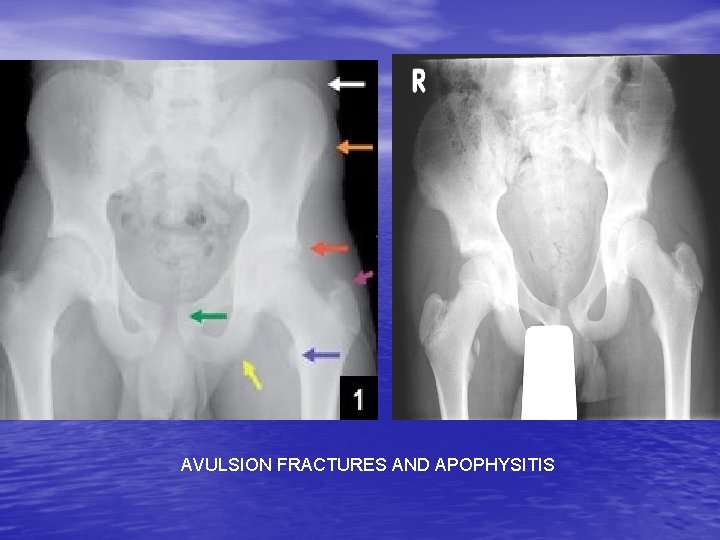

PELVIC CONDITIONS • Hip Pointer: contusion to the iliac crest • Osteitis Pubis: Pull of muscles from the pubis. Common in runners • Athletic Pubalgia: Chronic pubic region pain. • Stress Fx • Avulsion Fx and apophysitis: Inflam of the apophyses of the hip

AVULSION FRACTURES AND APOPHYSITIS